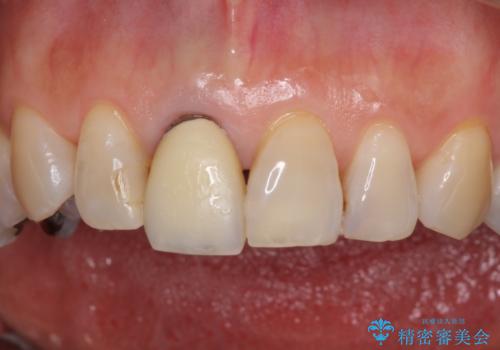

金属を全てセラミックに メタルフリー治療

- 口腔内にある銀歯を全て外したいとのことで来院された患者様です。

土台に含まれている金属も含め、口腔内の金属は全て除去し、抜歯しなければならない歯は抜歯し、オールセラミッククラウンやセラミックインレーにて治療することとしました。